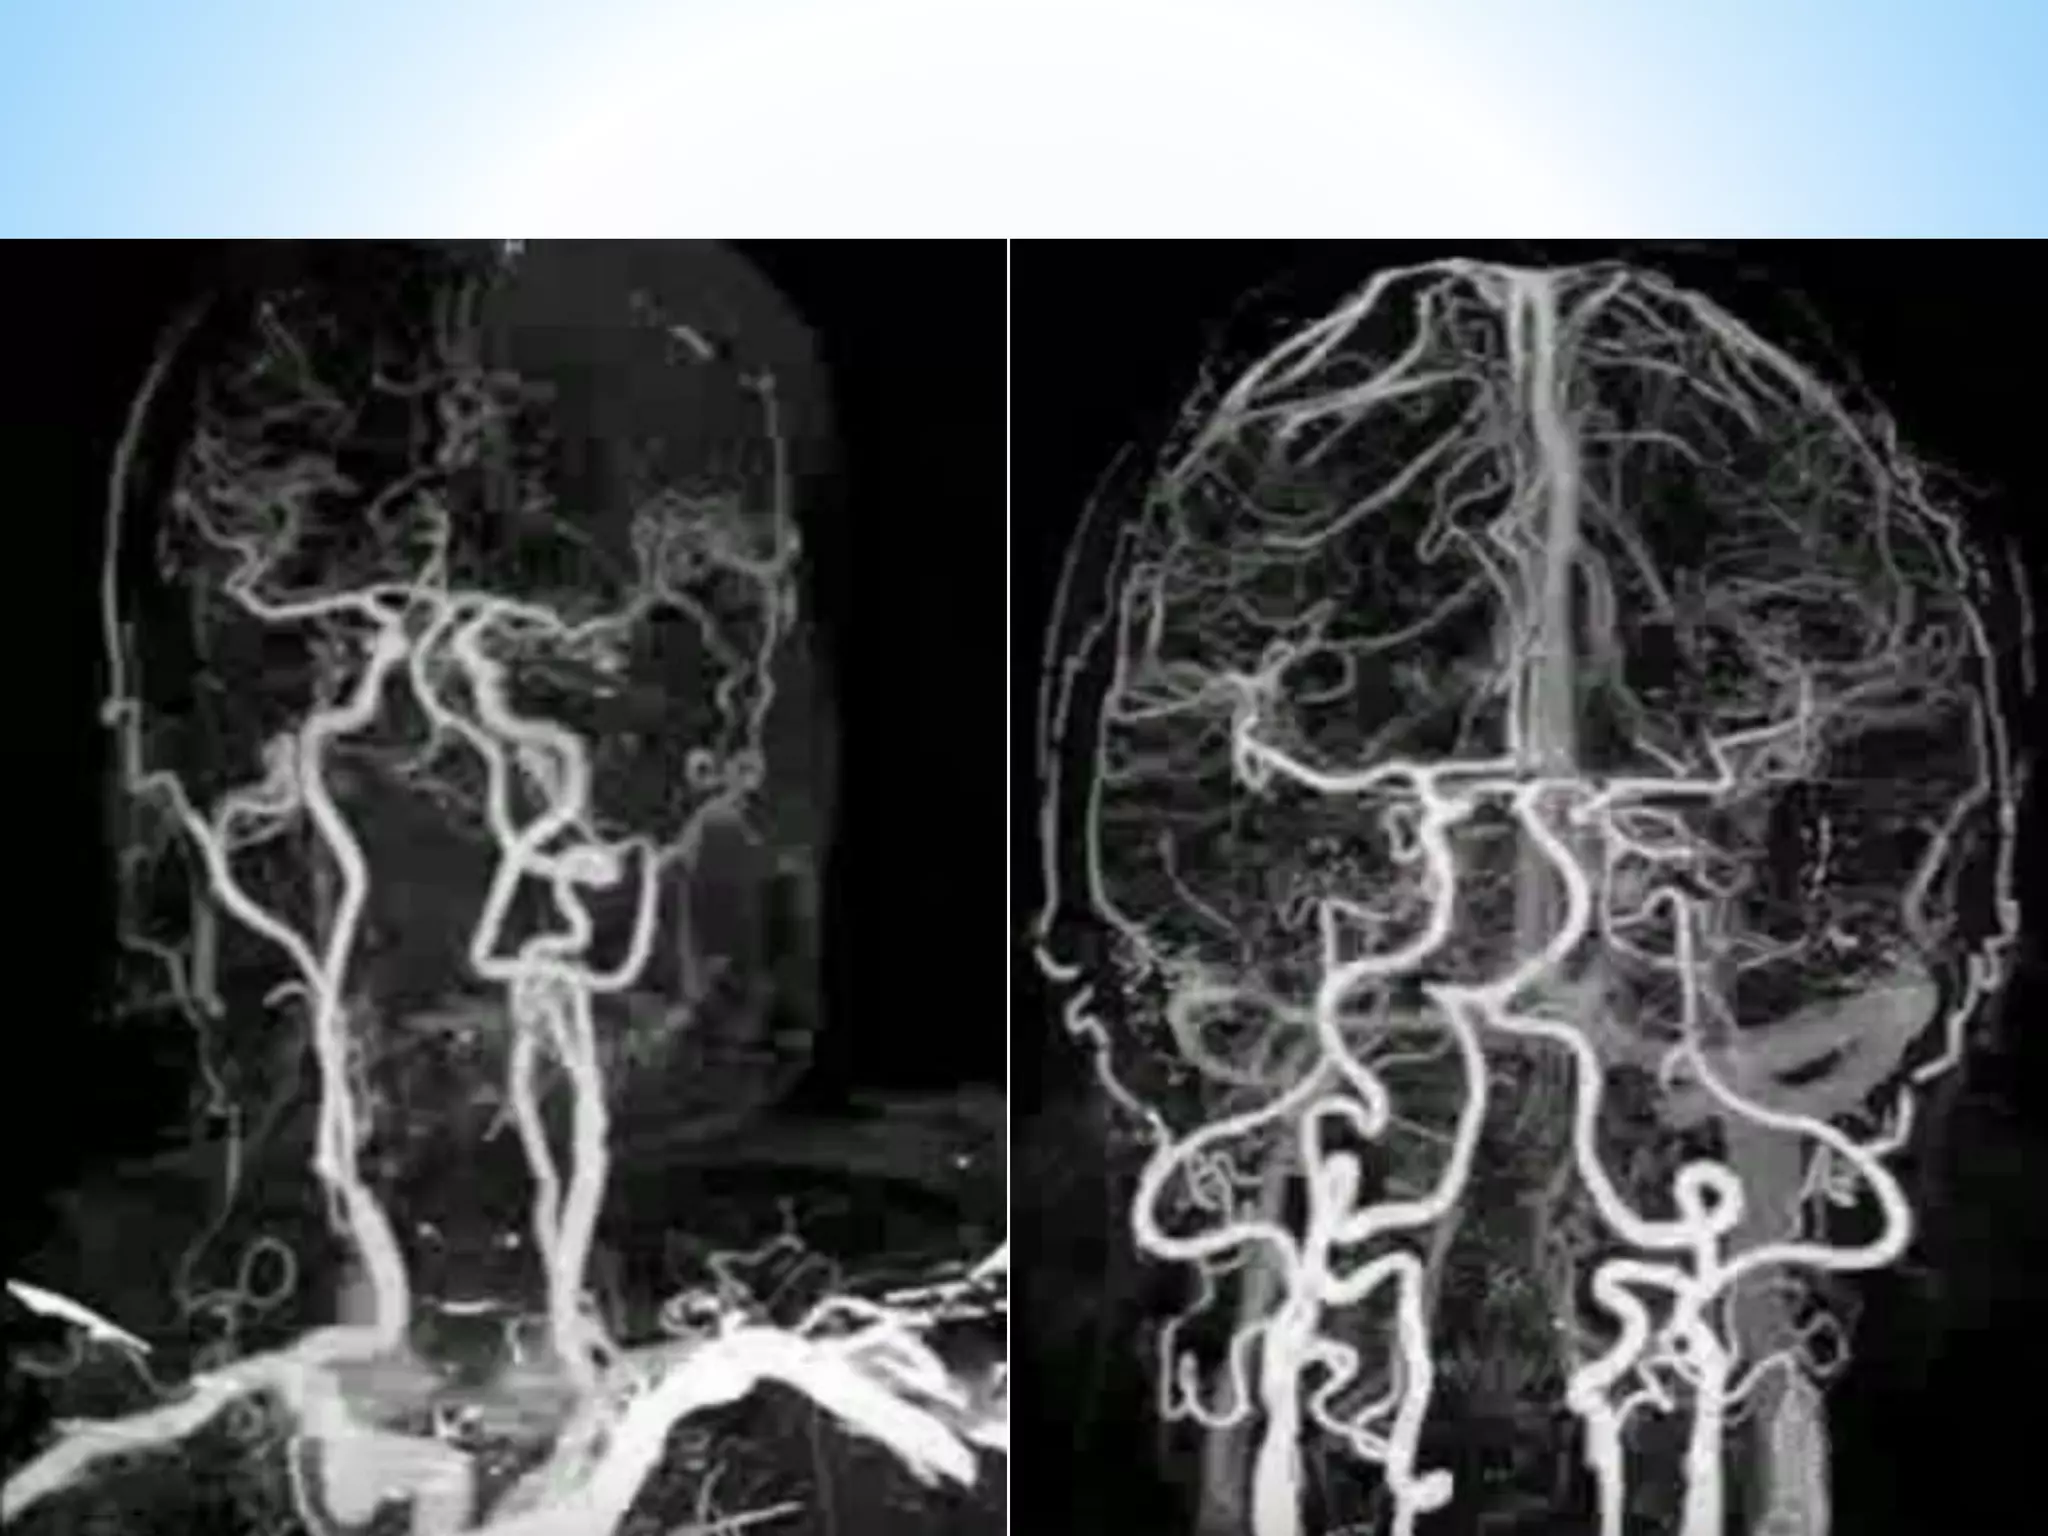

CT Dual EnergyStat-Of-Art new technology CT Angiography of brain

Comparison of automatedbone removal algorithm for dual-energy CT (A) and conventional bone removal CT angiography (B). The dual-energy CT image is superior in quality and although larger bone remnants are retained, the vasculature can be well assessed. Dual Source conventional

Comparison of automated bone removal algorithm for dual-energy CT (A) and conventional bone

removal CT angiography (B). The dual-energy CT image is superior in quality and although larger

bone remnants are retained, the vasculature can be well assessed.

Dual Source conventional